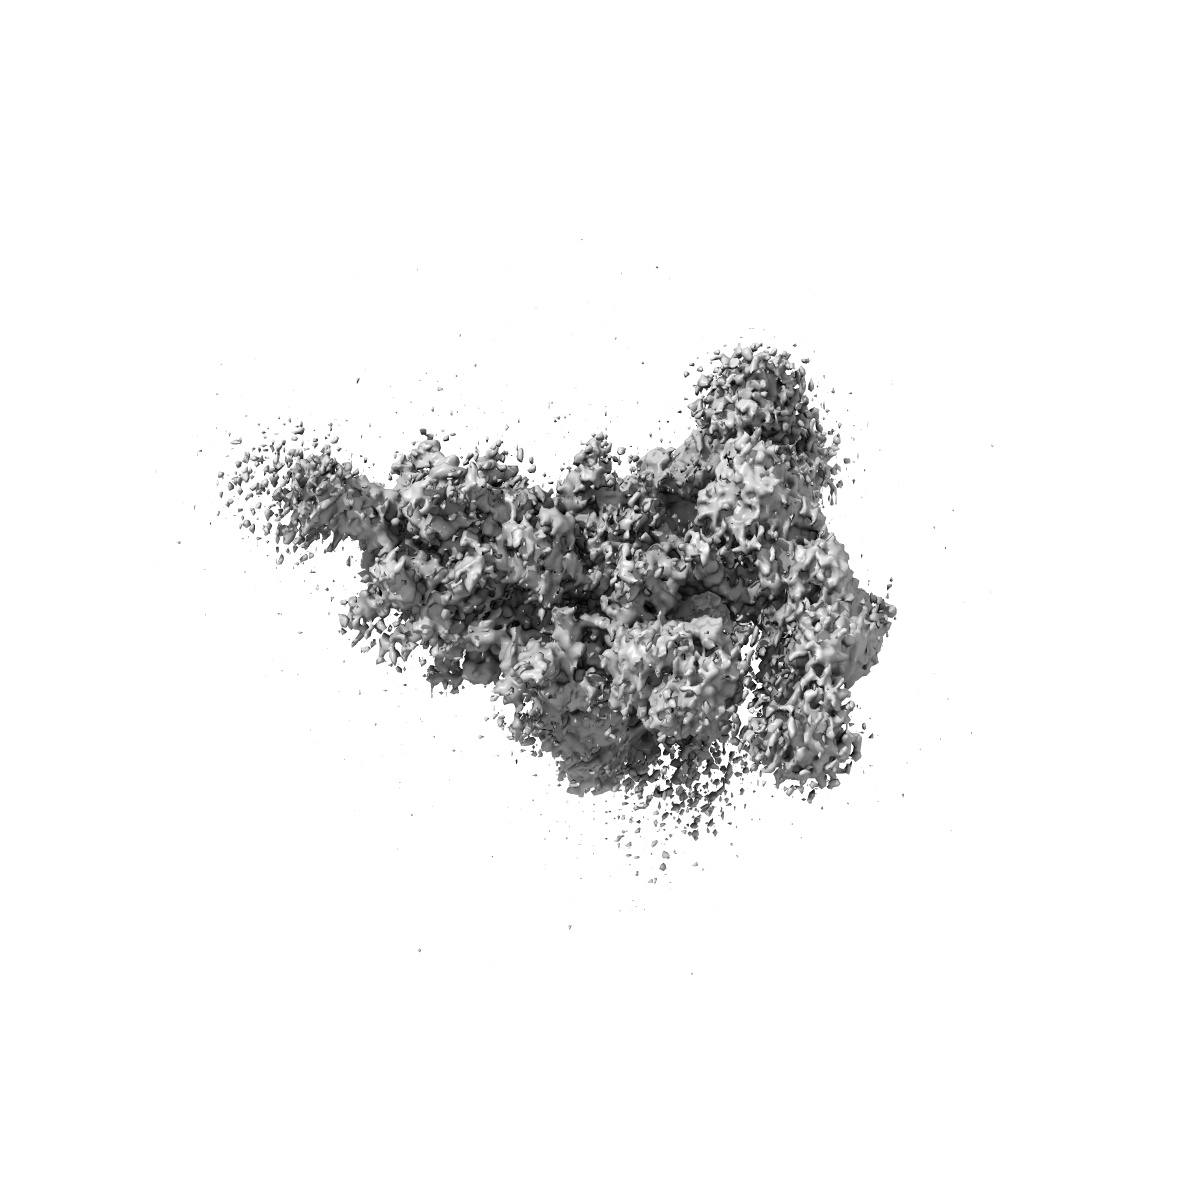

SARS-CoV-2 spike trimer (6P) in complex with two H18 and two R1-32 Fabs

Single-particle3.96 Å

Sample: SARS-CoV-2 spike trimer (6P) in complex with two H18 and two R1-32 Fabs